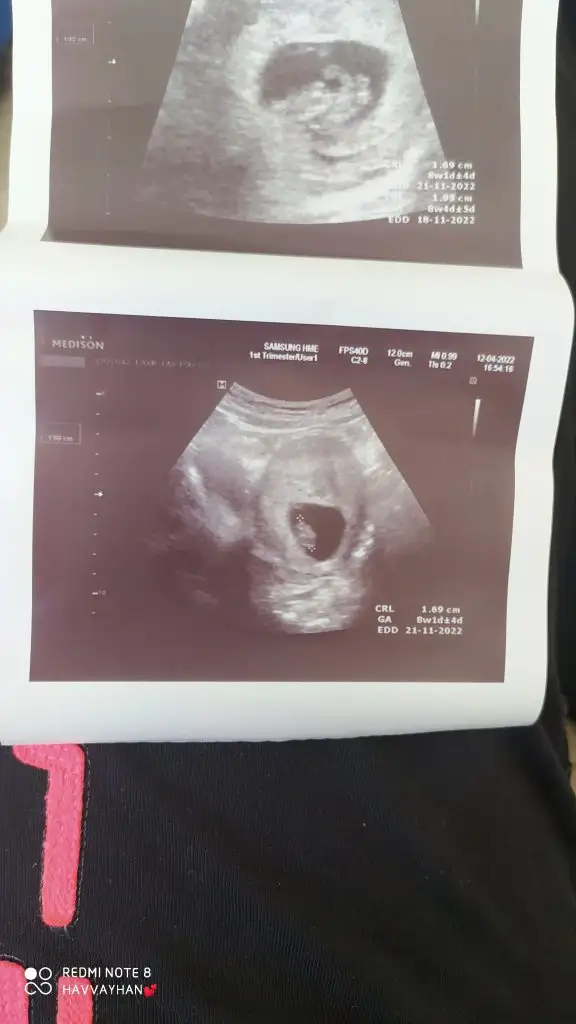

5 ve 14. haftaya kadar olan ultrason fotolarınızı paylaşın. Vajinadan mı yoksa karından mı çekildiğini ve kaç haftalık olduğunu da mutlaka belirtin.:anneadayı:

Karından ultrason kagidim tahmin edermisiniz acaba

• Screenshot_2022-05-01-08-18-19-356_com.miui.gallery.webp

Screenshot_2022-05-01-08-18-19-356_com.miui.gallery.webp

13,4 KB · Görüntüleme: 81